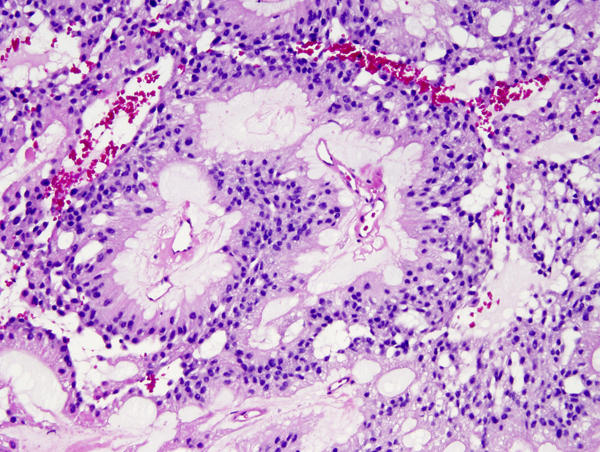

Microscopically, the tumor cells resemble normal ependymal cells and are arranged in perivascular pseudorosettes (tumor cell nuclei located at some distance from a central vessel with delicate processes radiating toward the vessel wall), tubular structures like the central canal of the spinal cord, and papillary formations. Ependymoma has distinctive ultrastructural features, including cilia, microvilli, and desmosomes. Ependymomas are graded as grade II or III according to the WHO system. Most are low-grade (WHO grade II). Some have increased cellular density, mitoses, necrosis, and microvascular proliferation while retaining the typical ependymoma tissue pattern (anaplastic ependymoma, WHO grade III).